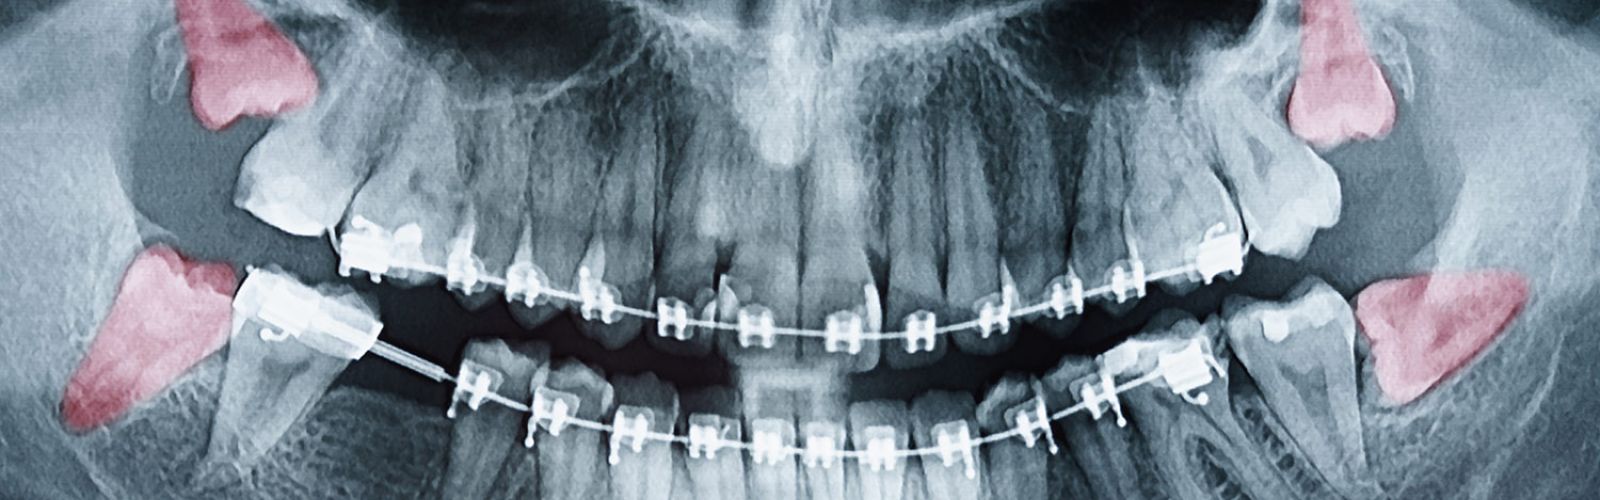

Sollten die Beschwerden nicht abklingen oder regelmäßig wiederkehren, empfiehlt sich ein Besuch beim Zahnarzt oder Kieferchirurgen. In der Praxis wird zunächst eine genaue Untersuchung und Röntgenaufnahme durchgeführt, um die Lage der Weisheitszähne und mögliche Risiken einzuschätzen. Häufig werden Weisheitszähne operativ entfernt, insbesondere wenn sie nicht vollständig durchbrechen oder schief wachsen und dadurch andere Zähne beeinträchtigen.